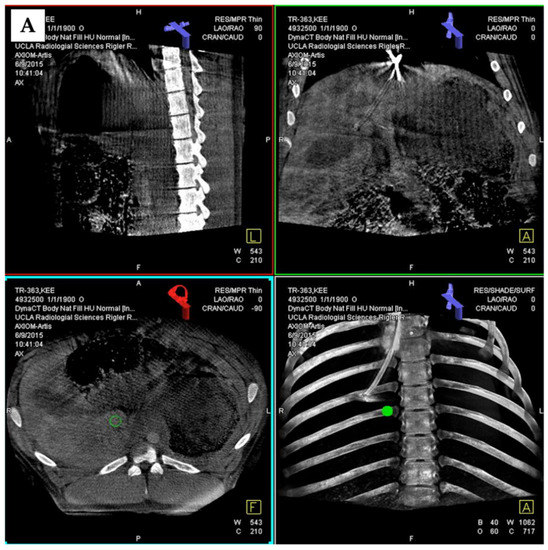

3.4. 3D Angiography-Guided DIPS Using CT/CBCT/Angiography-Fused Images